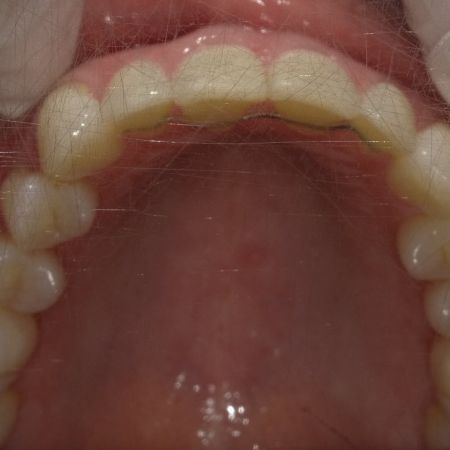

Nach der Behandlung

(Dauer der aktiven Behandlung: Im Oberkiefer 7 Monate, im Unterkiefer 1 Jahr, 4 Monate)

Sehr gute Stabilität nach 12 Jahren